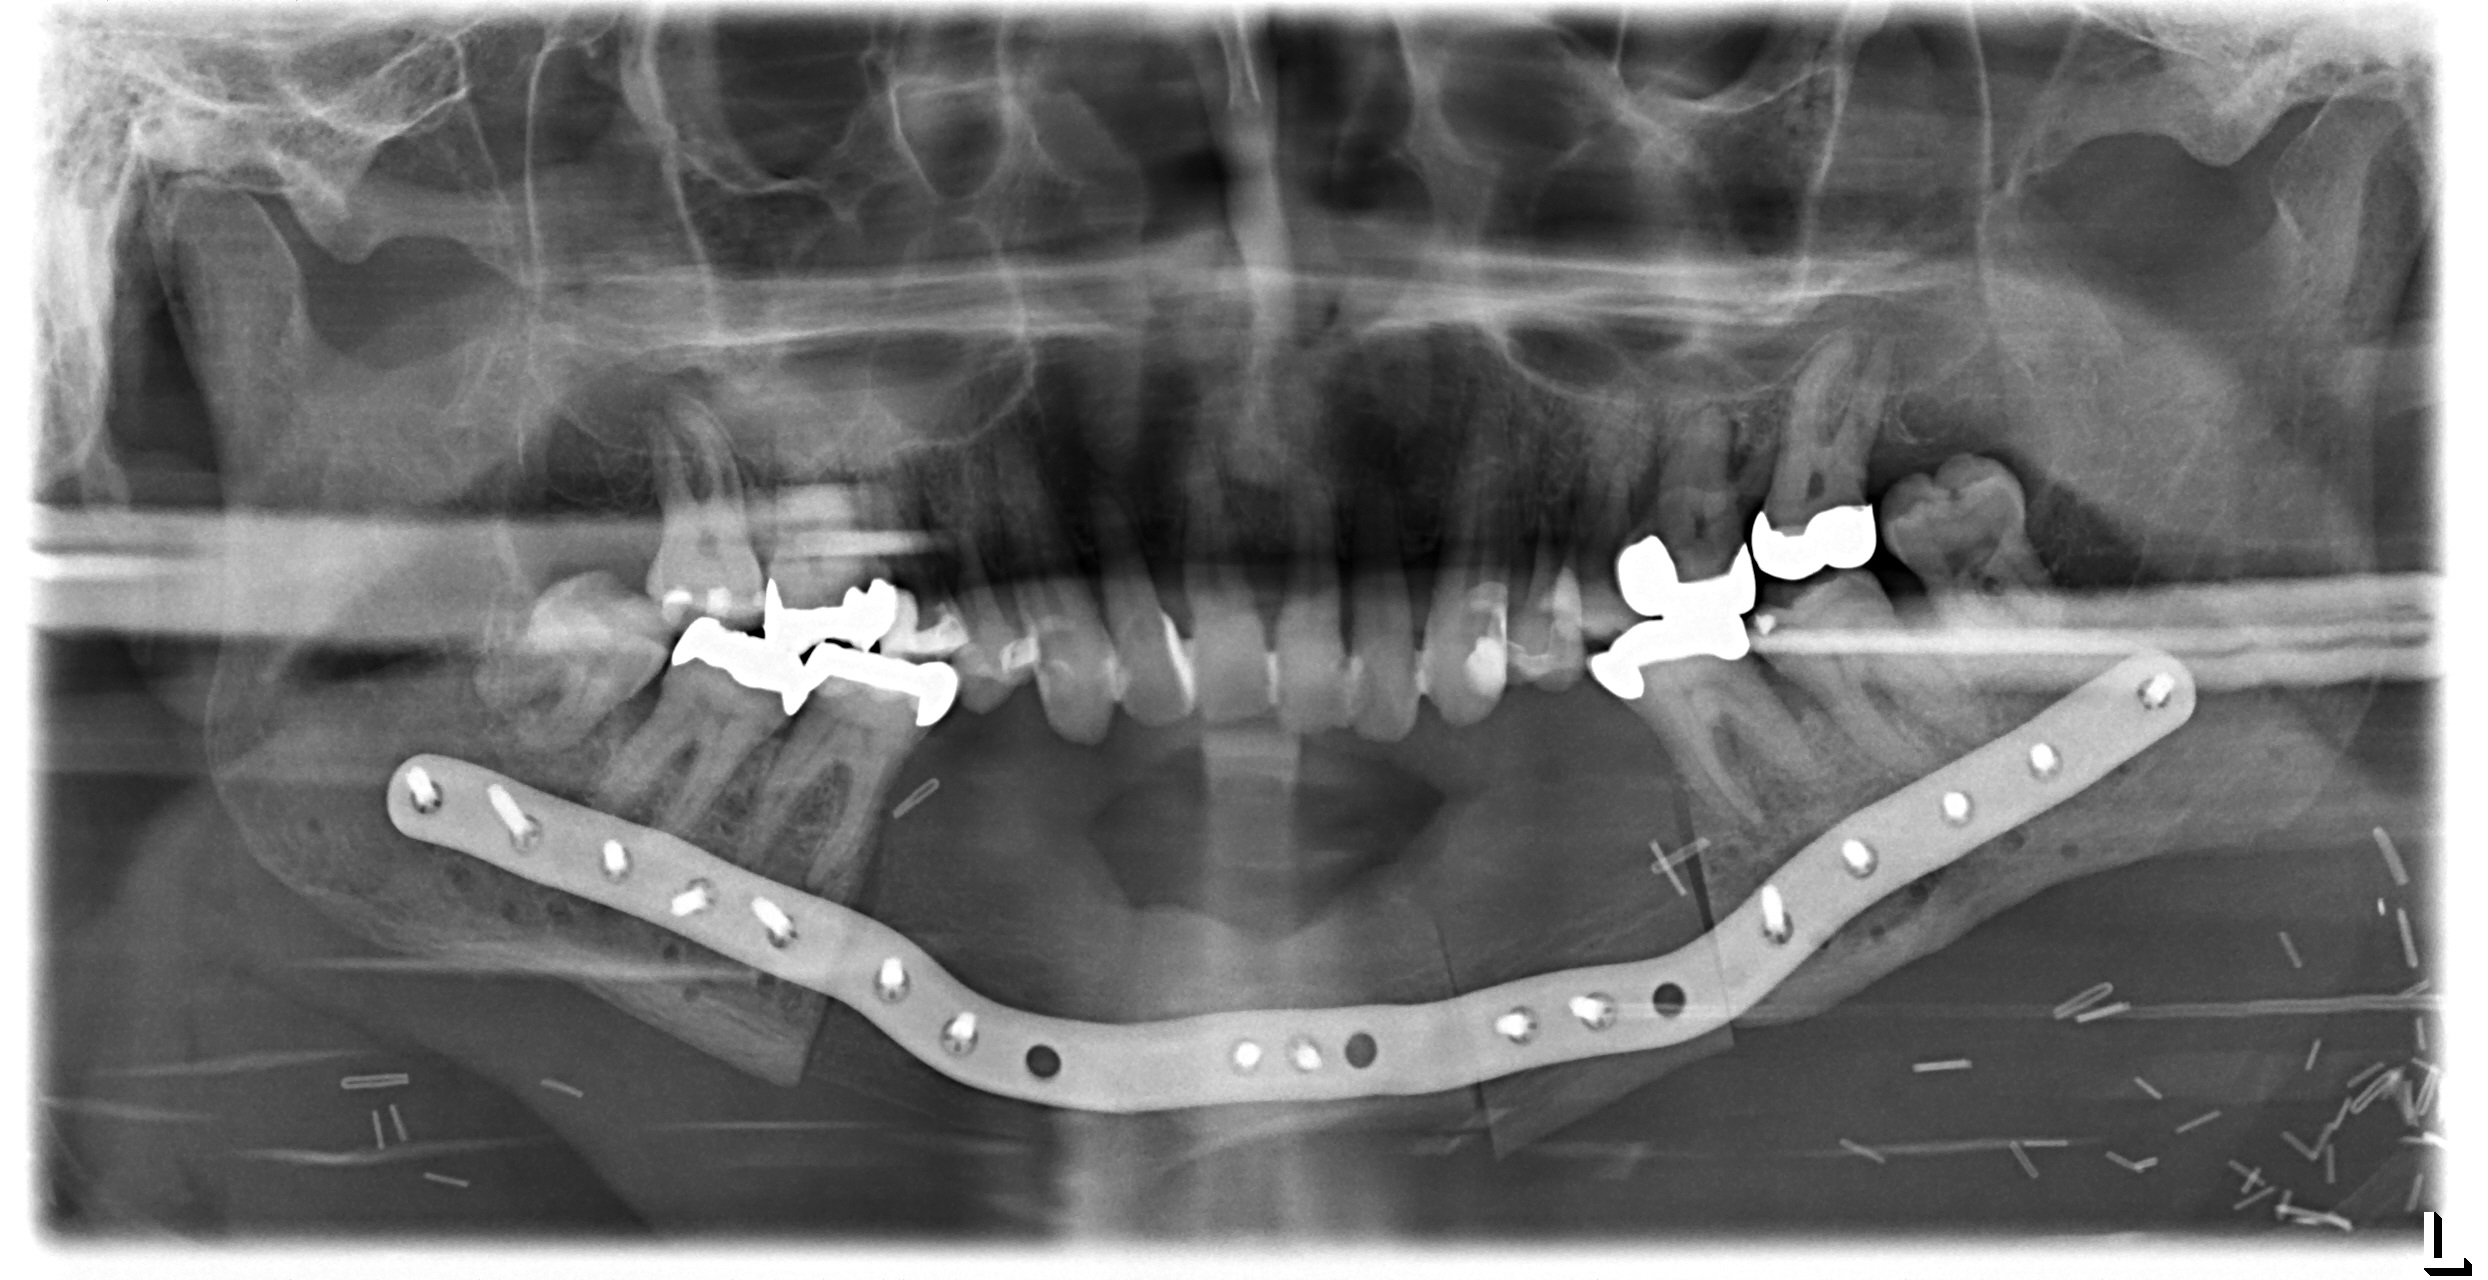

Postoperative imaging confirmed minimal intersegmental gaps to the mandibular remnants with undisturbed healing but limited overall bone volume (Fig. 7a-c). Therefore removal of the PSPMP and a preimplantological augmentation with corticocancellous iliac bone grafts followed 16 months later.

Finally, dental implants were inserted (Fig. 8).